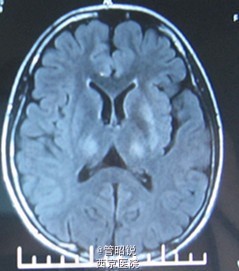

肝豆状核变性一例

主诉:右手抖动、无力1年 现病史:2014年9月无明显诱因出现右手抖动,情绪激动、写字或拿筷子时明显,呈间断性,并感右手无力,写字时明显。日常生活不受影响,未予治疗。近1月,家人发现其写字无力明显,遂就诊我院门诊,化验铜:9.9umol/L;铜蓝蛋白 3.2mg/dL;甲功 TSH 6.31uIU/mL。头颅CT示:双侧基底节区多发片状低密度灶,建议进一步检查。

肝豆状核变性 入院后治疗:青霉胺125mg/L 2/日